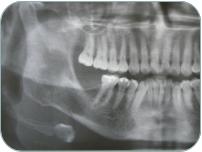

Camino Dorado #18, Planta alta; Fracc. Camino Real, Cándiles, Corregidora, Querétaro. Made with Xara Odontología Pediátrica El odontopediatra será, el encargado de explorar, diagnósticar y  tratar al paciente infantil. También se encarga de detectar posibles anomalías en la posición de los maxilares o dientes  y de realizar un tratamiento en caso de ser  necesario. La principal diferencia entre la odontología habitual y la odontopediatría en el tratamiento de caries es la presencia de los dientes temporales  (dientes de leche) lo cual hace que el tratamiento cambie en los niños, de tal forma que las lesiones ocurridas en la dentición temporal se tratarán de una manera completamente diferente a los dientes permanentes de los adultos, evitando así un tratamiento inadecuado en un diente temporal que luego repercutirá en su sucesor. Odontología Integral Por que creemos en la prevención,  fomentamos el cuidado y la higiene dental tomando en cuenta las habilidades de cada uno de nuestros pacientes, OK&F te ofrece un programa personalizado, necesario para adoptar medidas destinadas a mejorar la salud bucal y así evitar problemas dentales futuros. Por otro lado, si ya presentas problemas de salud bucal, te ofrecemos los tratamientos adecuados para llevarte a un estado de salud óptimo, utilizando siempre materiales de la más alta calidad. Patología Bucal Se encarga de la identificación y tratamiento de las alteraciones y enfermedades localizadas en la cavidad oral comprendiendo todas las estructuras que lo conforman. La patología bucal estudia las causas, procesos y efectos de las enfermedades que aquejan al complejo oral y maxilofacial; incluye la investigación y diagnóstico usando exámenes clínicos, radiográficos, microscópicos, así como el manejo de la enfermedad.